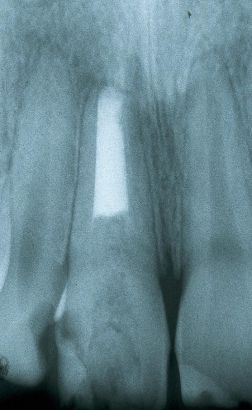

Este paciente se presentó con la queja principal de incomodidad en el funcionamiento de los dientes anteriores inferiores. Nótese la pérdida y recesión de encía.

La evidencia clínica de una enfermedad periodontal grave fue respaldada por las pruebas radiográficas en las que se observa una pérdida de hueso de más del 70% en los incisivos mandibulares y la presencia de un grado de movilidad 2 para los cuatro incisivos.

Las radiografías de la férula acabada verifican la unión de los incisivos con periodontitis.

Desde un punto de vista incisal la férula tiene un volumen mínimo. Las radiografías de la férula acabada verifican la unión de los incisivos con periodontitis. La radiografía muestra como la fibra está incrustada en el composite.